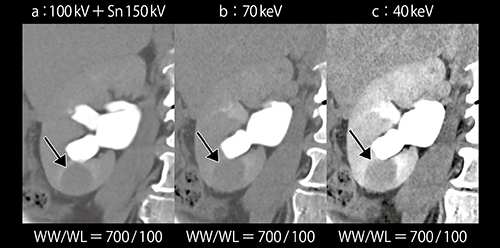

また,腎部分切除術では,腎杯損傷防止のためCT Urography(CTU:排泄相)にて腎杯と腫瘍との距離を確認する必要があるが,排泄相では腎実質の造影の低下により,腫瘍のコントラストが不十分となる。Dual Energy ImagingのMono+は,従来よりもSNRに優れた仮想単色X線画像を作成可能である。120kV相当の画像である100kV+Sn150kV画像では不明瞭な病変も,Mono+の40keV画像ではコントラストが明瞭となる(図2)。

図2 Mono+の40keV画像(c)による腎腫瘍の描出

続いて撮影した腎実質相および排泄相では造影剤量が不十分であるが, Mono+の40keV画像により,ノイズが増加することなく腎実質の造影効果が増強し,腫瘍と腎実質のコントラストが確認できた(図6)。また,わずかに尿路に排泄された造影剤と腫瘤とのコントラストも得ることができた(図7 b↓)。

図6 症例2:Mono+の40keV画像による造影剤20mLでの腎実質相の描出